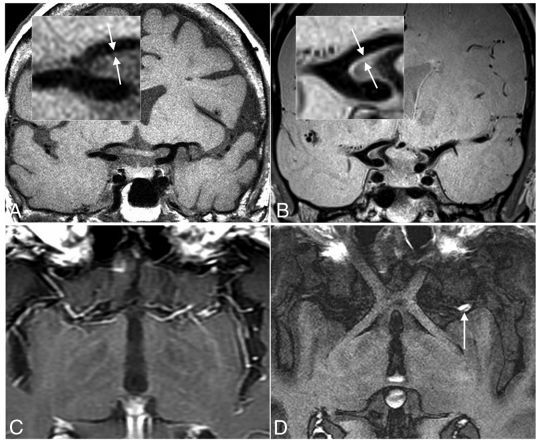

图1.VW-MR成像的技术实现。

比较健康志愿者冠状面2D T1加权FLAIR VW-MR成像序列(A)和3D质子密度加权可变翻转角重新聚焦脉冲,快速自旋回波VW-MR成像序列(B),插图显示颈动脉终端的放大图像,箭头指向管壁,对照的标准对比增强T1加权自旋回波序列(C)和优化对比增强的T1加权VW-MR成像序列(D)显示了血液抑制,左侧MCA M1段显示增强性动脉粥样硬化斑块(箭头)。

3T场强,2D序列,2.0X0.4X0.4mm 体素,可以合理平衡空间分辨率和信噪比,扫描2至4厘米厚的组织的时间约为5-7分钟(图1A)。

3T场强,3D序列,0.5X0.5X0.5mm体素是合理的的起点(图1B),在7-10分钟内,可以覆盖Willis环和第二/三阶分支。很多有经验的中心正在使用各向同性的0.4-0.7mmde 体素维度用于3D采集。

血管壁的MR成像表征需要抑制来自腔内血液和脑脊液(或靠近大脑的血管的脑实质)的磁共振成像信号(图1C,-D)。